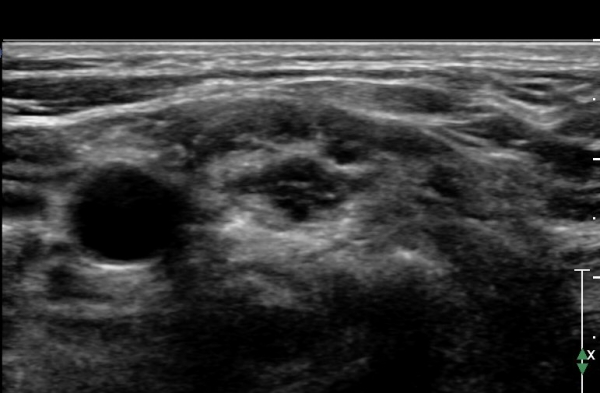

ŽÃËÀÚ¸¦ Á¶±Ý ¸»´ÜÀ¸·Î À̵¿ÇÏ¿© Àü»ç°¢±Ù°ú Á߻簢±Ù »çÀÌ¿¡¼­ »ó¿Ï½Å°æÃÑÀÇ Àú¿¡ÄÚ ºÎÁ¾ÀÌ °üÂûµÊ                  (»çÁø 2, 3).